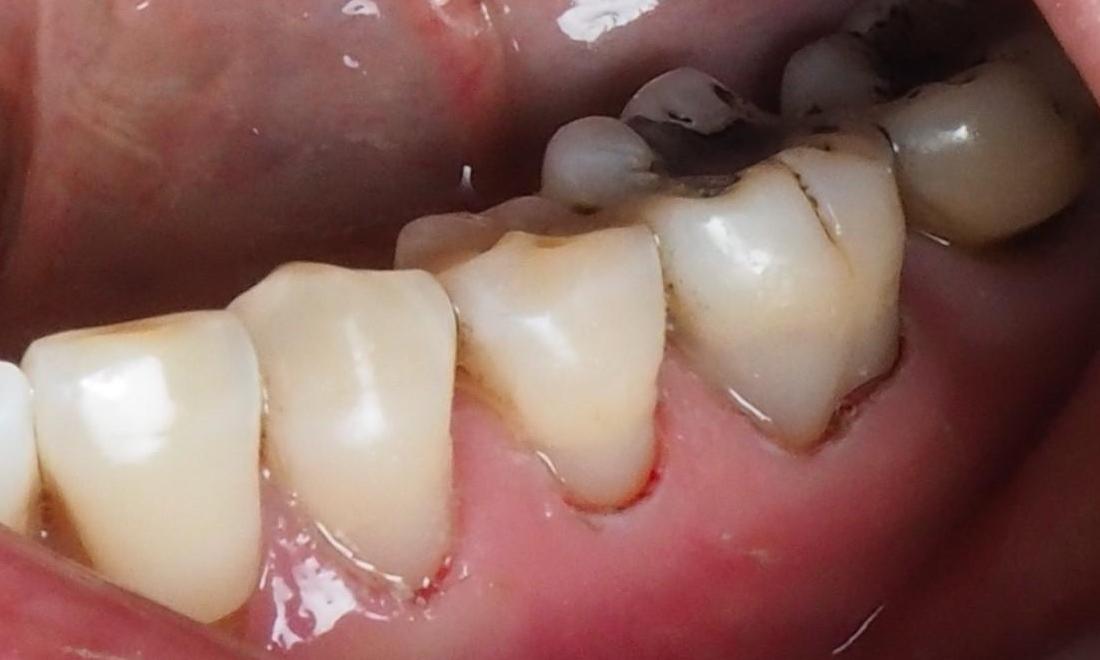

Mrs. J. didn't know anything could be done for the discolored wear areas on her back teeth. After one visit with Dr. Karian, these teeth are reinforced and beautiful again!